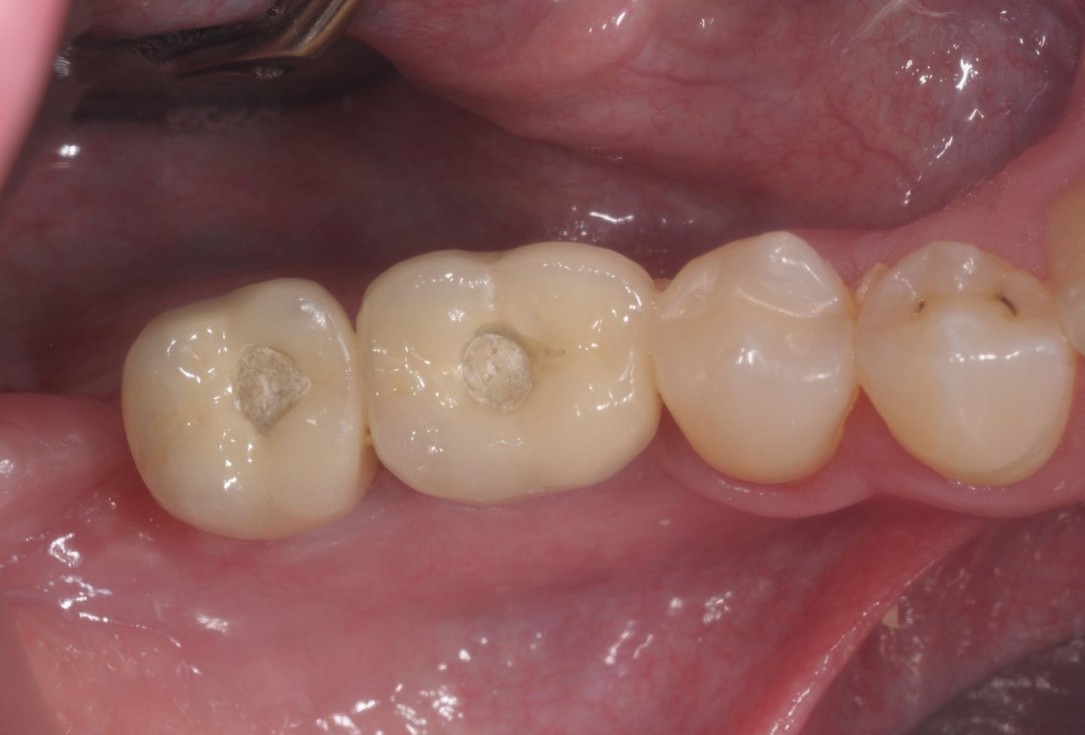

26/28 - Final prosthetic restauration with provisional screw channels - occlusal viewThree-dimensional augmentation with maxgraft® cortico - Dr. R. Würdinger